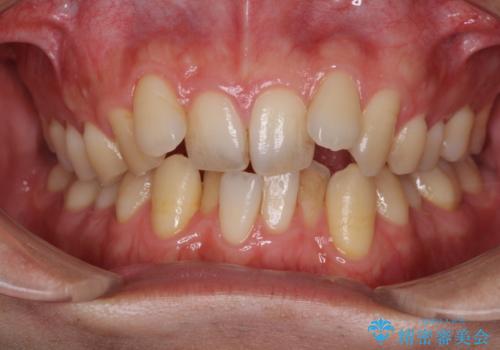

- 左上4番と左上6番が欠損しており、欠損部にはさまれた左上5番が後ろ側に倒れている状態で来院されました。

左上4番はインプラント、左上6番はブリッジにて治療することとなりましたが、左上5番が傾いているのでこのままではインプラント正しい位置に入れにくく、かぶせ物が正常な形態で装着できなくなり、ブリッジも装着が困難となります。

そこで、部分矯正をして左上5番を正しい位置に戻してからインプラント・ブリッジ治療をしていくこととなりました。